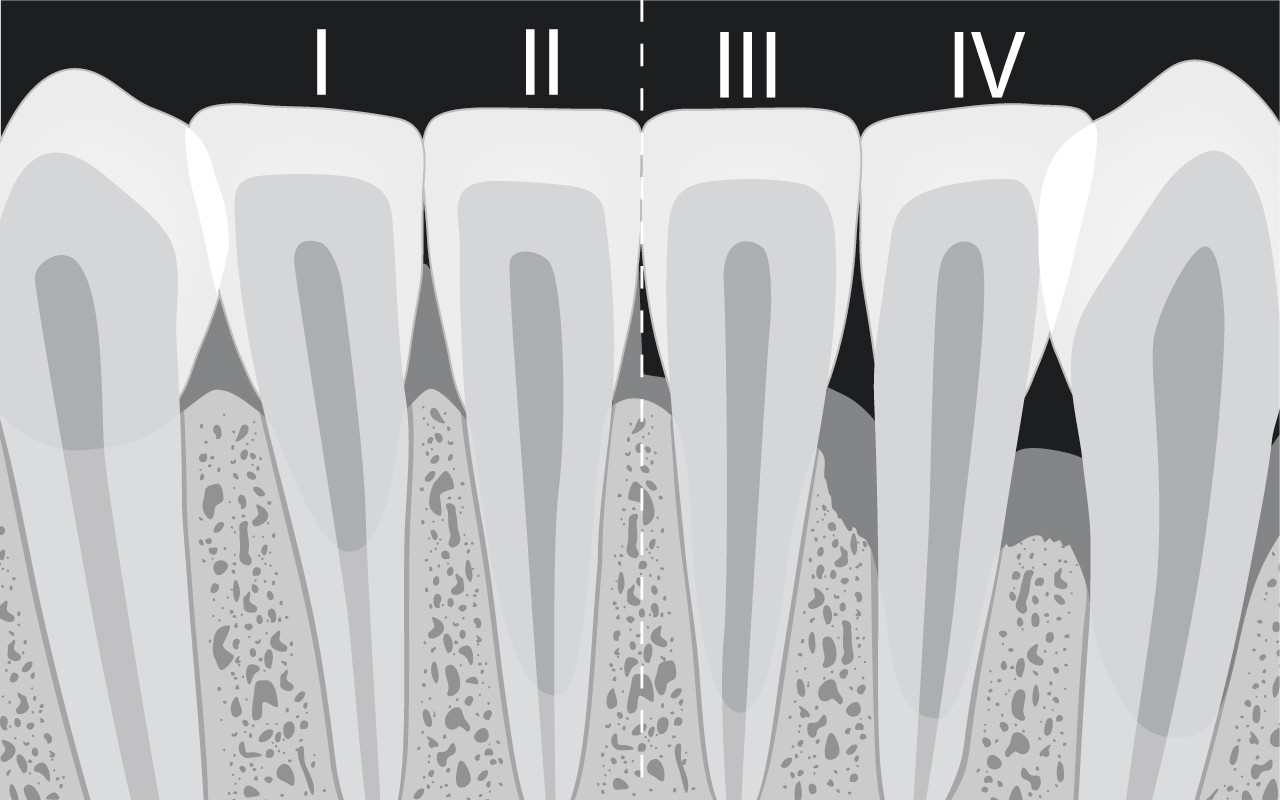

Schweregrad der Zahnfleischrezession

Zahnfleischrezessionen werden in unterschiedliche Schweregrade eingeteilt. Je nach Schweregrad stehen nur eine geringe Auswahl von Behandlungsmöglichkeiten zur Verfügung.

Bei Zahnfleischrezessionen werden vier Schweregrade voneinander unterschieden, weil sich daraus auch die Behandlungsmöglichkeiten herleiten lassen.

Eine einfache Rezession liegt vor, wenn die Rückbildung des Zahnfleischrandes noch nicht bis zur beweglichen Mundschleimhaut vorgedrungen ist. Beim zweiten Schweregrad ist die Rezession bereits in die bewegliche Schleimhaut vorgedrungen. In beiden Fällen ist die Korrektur des Zahnfleischrandes mit einem chirurgischen Eingriff möglich.

Da bei den Schweregraden 3 und 4 bereits auch Kieferknochen zwischen den Zähnen abgebaut worden ist, können dort vorhandene Zahnfleischrezessionen auch nicht mit chirurgischen Massnahmen vollständig korrigiert werden.